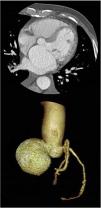

Los aneurismas del seno de Valsalva son una anomalía congénita rara, más frecuentes en varones, y habitualmente detectados en la edad adulta. Permanecen asintomáticos durante muchos años, y presentan alto riesgo de complicaciones como endocarditis infecciosa o rotura del aneurisma con comunicación a cavidades cardiacas y desarrollo de insuficiencia cardiaca aguda. Se presenta el caso de un varón de 69 años, con antecedentes de ictus hemorrágico por rotura de aneurisma cerebral 10 años antes, que ingresó por insuficiencia cardiaca en situación de edema agudo de pulmón. El electrocardiograma mostró ritmo de fibrilación auricular con respuesta ventricular a 140lpm. Se realizó cardioversión eléctrica con éxito y se inició tratamiento deplectivo con excelente respuesta clínica. Se realizó ecocardiografía transtorácica y transesofágica que mostró regurgitación aórtica leve y dilatación aneurismática del seno de Valsalva no coronariano de 5,7×4,3cm (fig. 1) que protruía y ocupaba la mayor parte de la aurícula izquierda condicionando la obstrucción al flujo transmitral (fig. 2), con el resto de aorta proximal normal. Se completó el estudio mediante una angiografía por tomografía computarizada, que mostró una placa mixta de predominio cálcico a nivel de la descendente anterior media que no causaba estenosis significativa, y confirmó la dilatación aneurismática aislada del seno no coronariano (fig. 3). Ante estos hallazgos se decidió tratamiento quirúrgico, y se realizó técnica de preservación valvular mediante sustitución de aorta supracoronaria y plastia del seno de Valsalva no coronariano. El posoperatorio transcurrió sin complicaciones.